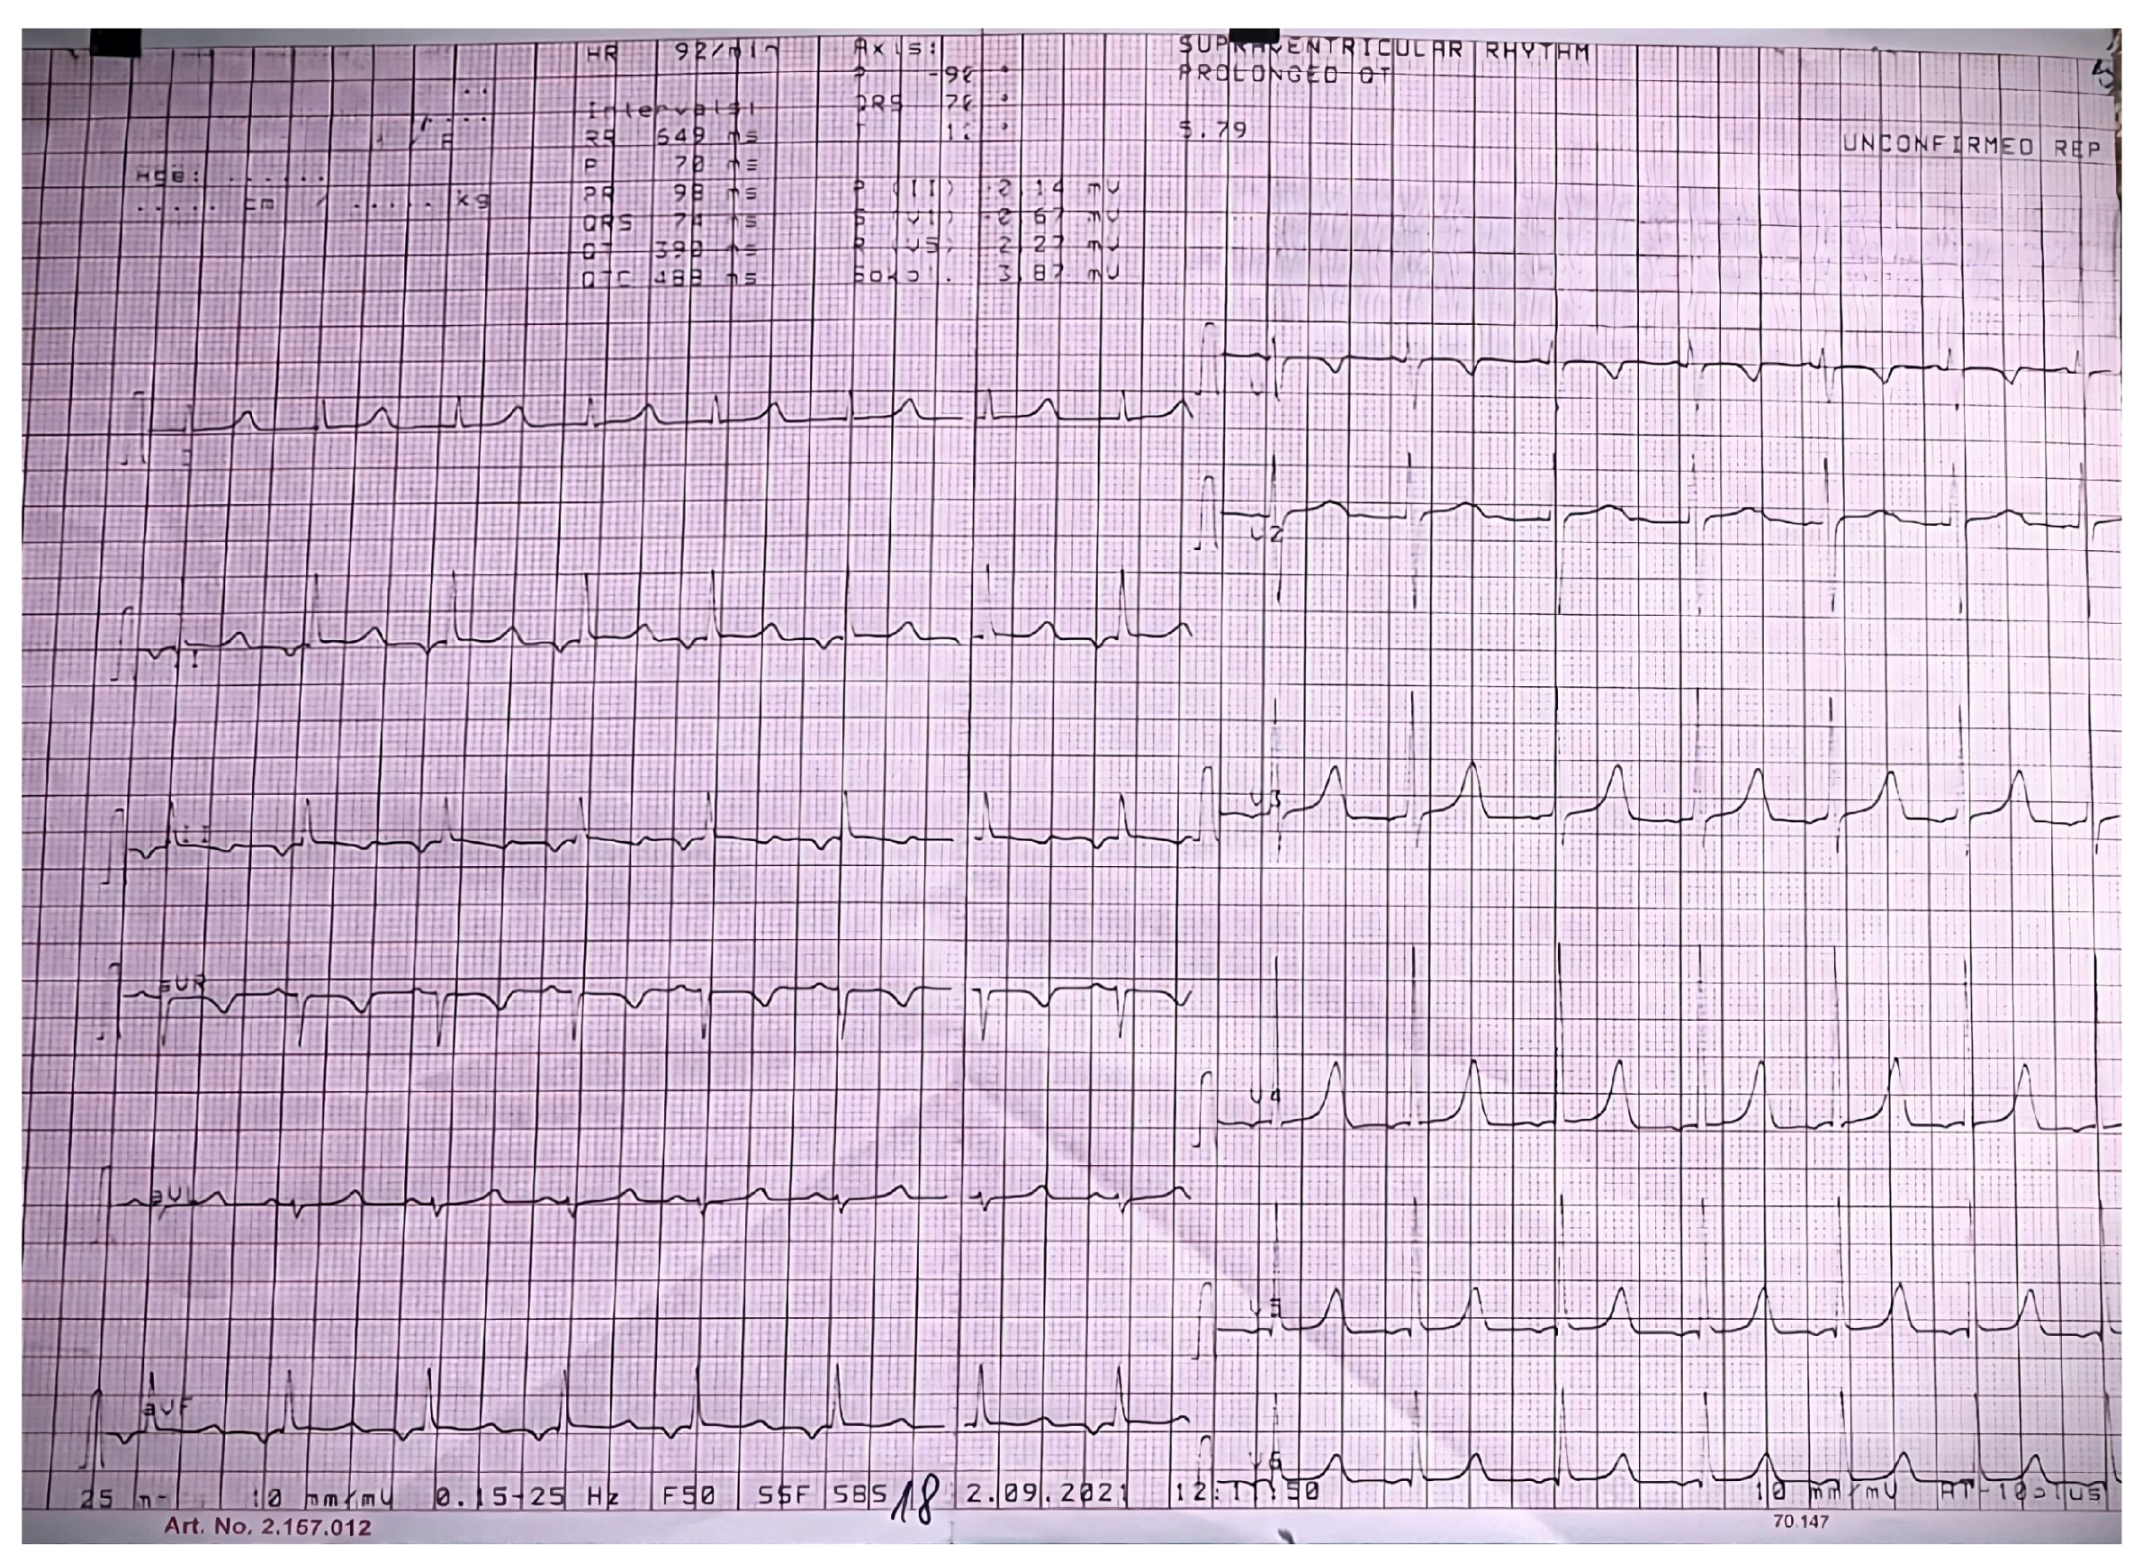

2.3. Biological and Paraclinical Assessment